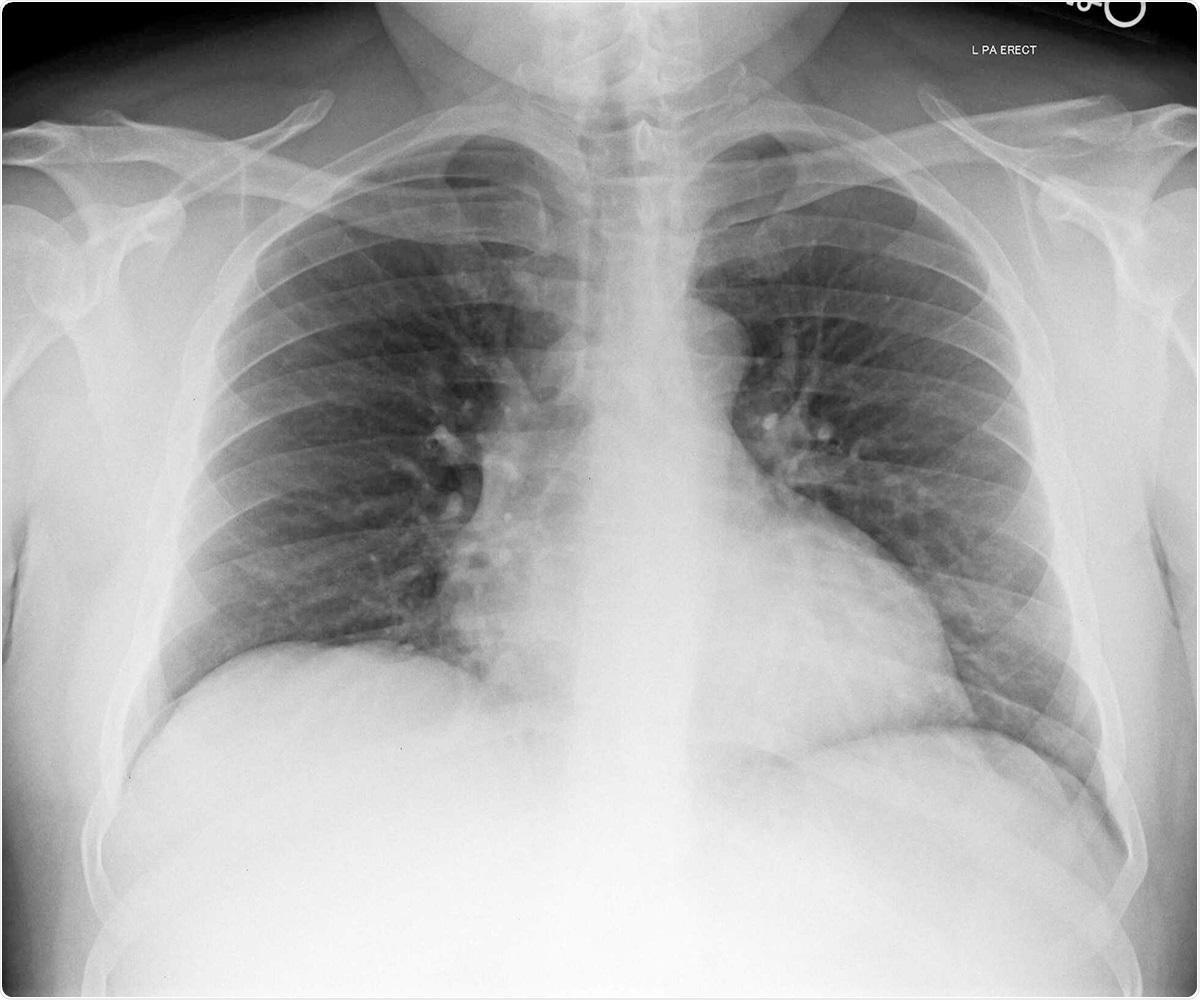

- Chest X-ray showed reduced lung volumes

Chest X-ray image of patient 3. Image Credit / Original Article.